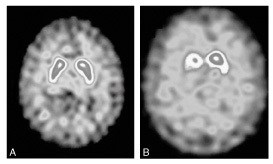

Quel est l’examen réalisé? Pourquoi l’a -t-on fait ? Quelle est l’origine probable des tremblements sur l’imagerie de gauche? celle de droite?

Scintigraphie cérébrale au DAT scann

réalisée pour distinguer un tremblement essentiel d’un tremblement parkinsonien à composante posturale

à gauche: tremblement essentiel car fixation normale

à droite: tremblement parkinsonien car diminution asymétrique de la fixation